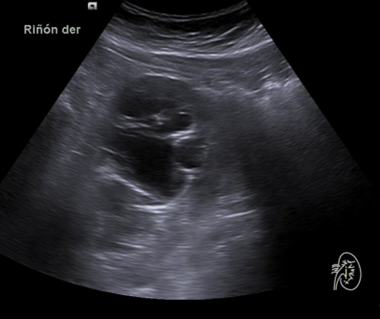

Riñón derecho 9,9 cm con morfología y ecogenicidad conservada. Presenta hidronefrosis grado III. No se identifica causa obstructiva.

Se remite a la paciente a Urgencias donde fue dada de alta con diagnóstico de CRU y tratamiento con Fosfomicina. Consultó al día siguiente, persistiendo el dolor y febrícula, remitiéndose de nuevo a Urgencias. Solicitan estudio de imagen con ecografía y ante los hallazgos se amplió el estudio a TC simple de abdomen: Hidronefrosis grado III con líquido perirrenal sugestivo de rotura de fórnix. Nefrolitiasis puntiformes en ambos cálices inferiores. Sin clara causa obstructiva objetivable. Se contactó con Urología de guardia quien propuso tratamiento ambulatorio con seguimiento posterior y colocación de nefrostomía programas y pielografía para estudio de probable estenosis de unión pieloureteral. Actualmente la paciente permanece en seguimiento por urología.